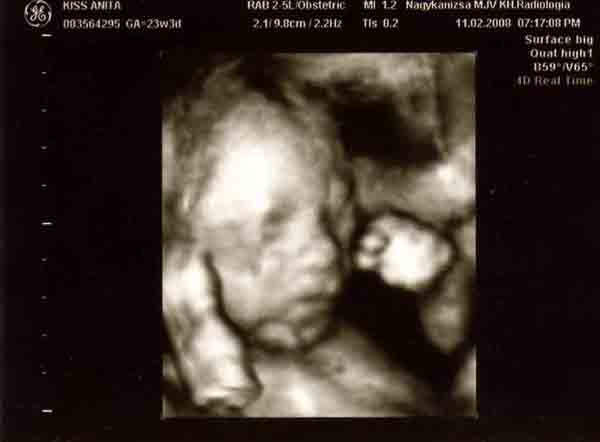

Bocsi,hogy bepofátlankodok,de mi múlt héten voltunk Kanizsán 4d-n.Tündér volt a doktornő.8000ft,20 perc a dvd és ad képeket.A Seffernél állítólag nincs kép,csak lemez.

A kanizsai telefonszám:Dr Nagy Éva 30/5265944

Kedden rendel délután fél 4-től

Mi másfél hetet vártunk,mert én kértem,hogy minél előbb mehessünk,mert ikrek és később már takarják egymást.Előbb viszont nem mertem menni,mert féltem,hogy még olyan kis ufósak lesznek.

Próbálok képet tenni róluk.

Kép [/img]

Kép

[img][img]https://www.babanet.hu/tarsalgo/attachments/1203443800.3007.jpg[/img]

Bocs,de csak külön-külön sikerült feltenni őket.[/img]

De édes babák! A mienken az arca nem látszott egyáltalán, úgy volt fordulva... :) A Seffernél voltunk, és valóban nem ad képet és 15000, majdnem duplája a kanizsainak

Nagyon édesek a törpék! És tényleg milyen jól látszódik a pofijuk.

Mi annó Veszprémben voltunk 4d-s uh-on. 10 ezret fizettünk, kaptunk videót, és 1 egész órán keresztül "szórakoztatott" minket a doki, ill. nézte, hogy minden rendben van-e. A Mátéról szembe, vagy ahol jól látszik az arca olyan kép sajnos nem készült, mert a Tóbi vagy befele fordult, vagy takarta az arcát a kezével 8) . Ennek ellenére hatalmas élmény volt. Mi egyébként 24 hetes koromban voltunk.